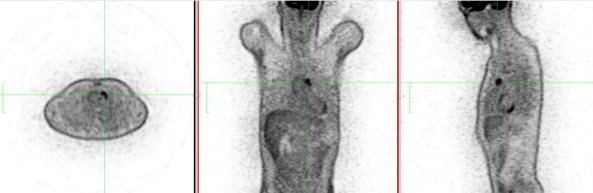

1. CT-Scan and PET-Scan

A 47-year-old male patient with no previous medical history was referred to the institution with a diagnosis of mediastinal mass suspected of being thymoma, without any clinical or laboratory signs of myasthenia gravis. The chest CT-scan showed a 2.5 cm lesion with no clear signs of infiltration of surrounding tissues and with a PET uptake of SUV max 4. The patient was scheduled for subxiphoid bilateral robotic-assisted thymectomy.